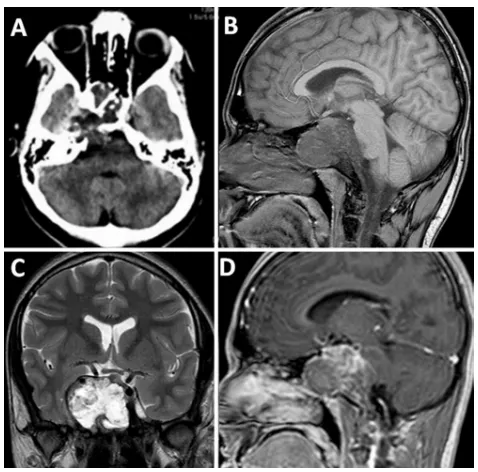

头颅CT扫描显示颅底存在巨大占位性病变,伴随斜坡上部骨质破坏。MRI检查证实存在以蝶骨斜坡区域为中心、侵犯右侧颞窝的轴外肿瘤。

术前影像评估:头颅CT扫描显示一巨大病变,侵蚀颅底骨质结构并侵犯右侧中颅窝。脑部磁共振成像证实,该肿瘤在T1加权像上呈现低信号,在T2加权像上呈现高信号,并在钆剂注射后显示对比增强。

术后MRI检查证实肿瘤已获得完全切除。术后出现短暂的右侧外展神经麻痹,与术中发现相符。在启动全身性皮质类固醇治疗后,神经功能缺损迅速恢复。

术后影像评估:术后矢状位T1加权平扫及增强磁共振成像,证实肿瘤已获得完全切除。